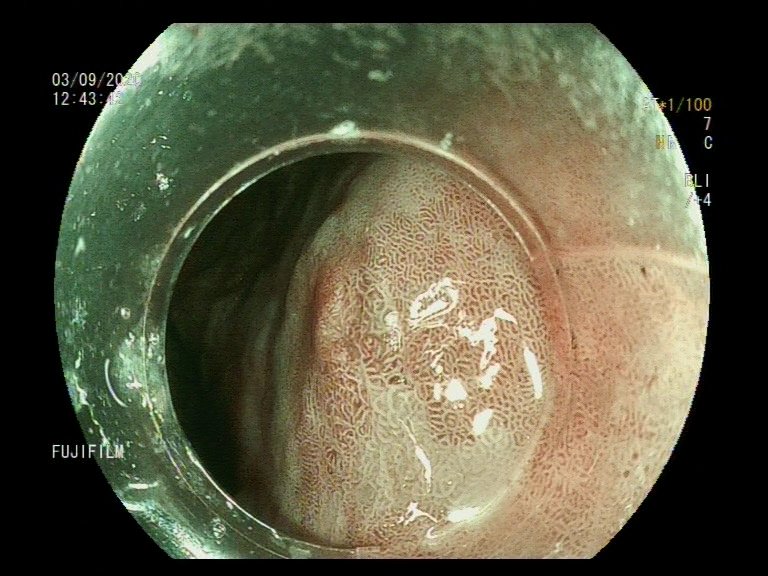

📢 March 2026 Issue #ACGCRJ 📷: Endoloop assisted hot snare polypectomy of a large brunner gland hamartoma in distal duodenum using colonoscope.🔦 🔗journals.lww.com/acgcr/pages/cu… @DushDahiya @DaniyalAbbasMD @AmCollegeGastro